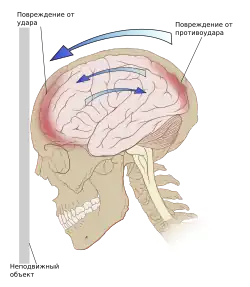

- Ушиб головного мозга: лёгкой, средней и тяжёлой степени (клинически). Ушиб головного мозга проявляется в ушибленной ране ткани мозга. Ушиб удар-противоудар наносится когда мозг ударяется о стенку черепа в месте непосредственного воздействия внешнего объекта на голову, получает одну ушибленную рану и затем ушибленная рана наносится на противоположную сторону мозга при резком замедлении движения ткани мозга. Клинические проявления зависят от расположения ушиба, и включают изменение психического состояния, повышенную сонливость, спутанность сознания, тревожное возбуждение. Небольшие интрапаренхиматозные кровоизлияния и припухлость окружающей ткани часто можно определить при компьютерной томографии.